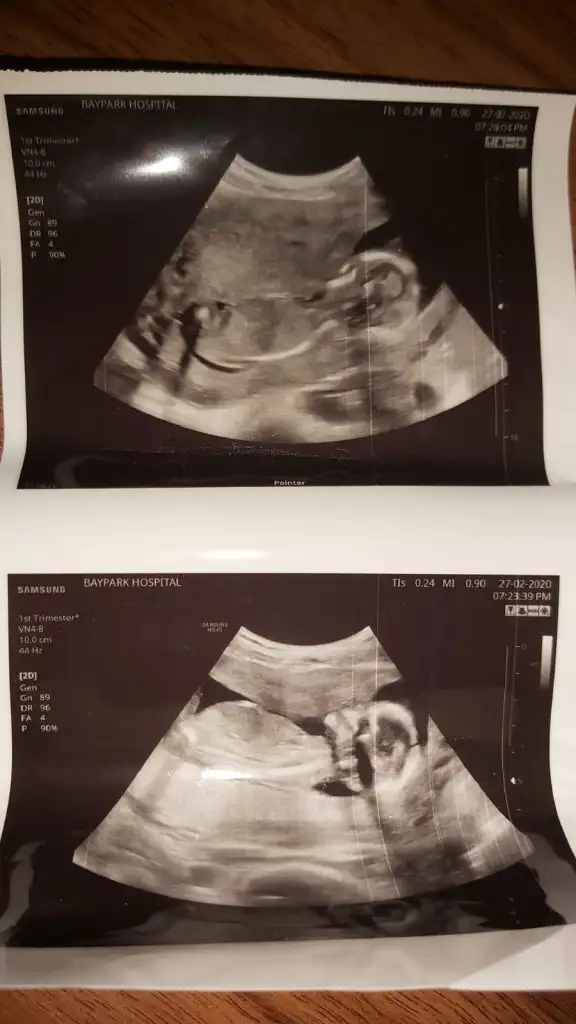

arkadaşımın yeni usg.. 15. hafta içinde ama doktor görememiş bacakları havaya dikmiş cinsiyetini görememiş.. tahmini olan var mı? gerçi artık nuba bakılamıyor sanırım bu haftalarda.. yine de var mıdır tahmininiz 😊

merhaba yine ben )

Daha öncede arkadaşın usg diye paylaşmıştımız aynı arkadaşmı benim tahminim neydi 😊